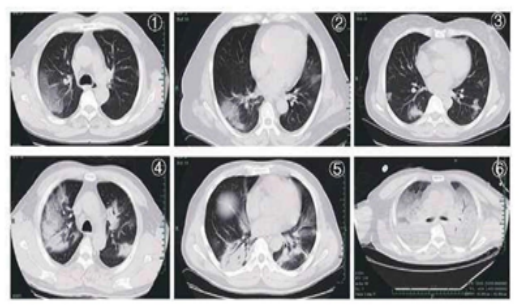

На КТ ОГК: характерные признаки COVID-19: Рис. 1, 2. Субплеврально очаги уплотнения по типу «матового стекла».

Рис. 3. Узлы и очаговая экссудация.

Рис. 4, 5. Многоочаговые уплотнения в пораженных участках.

Рис. 6. Диффузное уплотнение, т.н. «белое легкое».

На КТ ОГК: характерные признаки COVID-19: Рис. 1, 2. Субплеврально очаги уплотнения по типу «матового стекла». Рис. 3. Узлы и очаговая экссудация. Рис. 4, 5. Многоочаговые уплотнения в пораженных участках. Рис. 6. Диффузное уплотнение, т.н. «белое легкое».